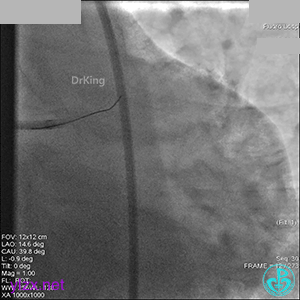

1周后再次上台,右冠脉3级血流,3段局限性严重狭窄,内膜模糊,应该是上次操作夹层遗留下的血肿。

先处理前降支开口严重狭窄并顺利植入前降支到左主干支架。